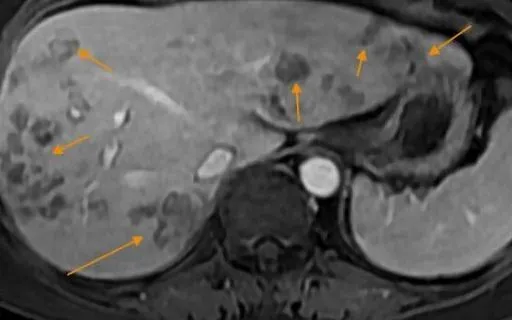

Kết quả xét nghiệm ghi nhận bệnh nhân dương tính với sán lá gan lớn và giun đũa chó mèo; siêu âm phát hiện ổ áp xe gan gần 5cm kèm tăng bạch cầu ái toan và chỉ số viêm. "Ổ áp xe khá lớn, nếu đến muộn có thể vỡ và gây nhiễm khuẩn huyết" - bác sĩ Hương cảnh báo.

Người bệnh được điều trị bằng phác đồ gồm chọc hút ổ áp xe, thuốc đặc hiệu diệt ký sinh trùng, kháng sinh kiểm soát nhiễm trùng và theo dõi men gan, bạch cầu ái toan. Sau điều trị, ổ áp xe thu nhỏ, không còn dịch mủ, triệu chứng ngứa và đau hạ sườn phải cải thiện rõ. Hiện sức khỏe bệnh nhân đã ổn định.